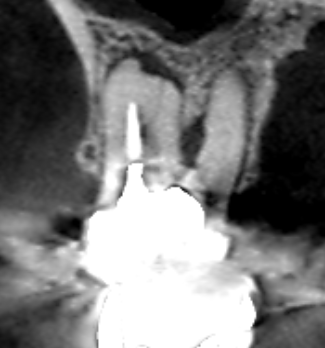

精密根管治療6カ月後の経過観察時の矢状断のCT画像です。上顎第一大臼歯の頬側2根共に根の先にみられた膿の影が消え歯槽骨が再生しています。